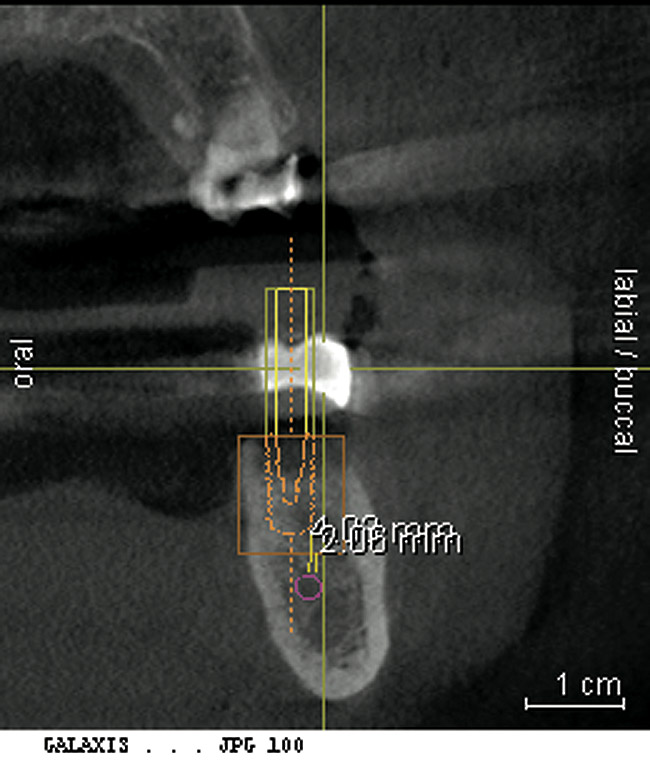

From a surgical perspective, the highest priority is the protection of vital anatomic structures from the trauma of surgery. When performing implant placement in the posterior mandible, it is critical to avoid trauma to the inferior alveolar neurovascular bundle (inferior alveolar canal) and prevent perforation of the lingual cortex. In a radiographic study, evaluating human CT scans, Quirynen et al reported on the variations of mandibular anatomy 4 mm to 6 mm anterior to the mental foramen.1 These authors introduced three classifications, based on the geometry of the mandibular bone and presence of lingual concavities and inclinations. Knowledge of the local anatomic situations in proposed implant sites can prevent potentially catastrophic injury during implant insertion. A CT scan affords the surgeon the opportunity to measure and appreciate the locations of these structures, but not the vertical and horizontal drill control necessary to be absolutely certain that inadvertent over-preparation or deviations do not occur. Many manufacturers sell so-called "drill stops," but these offer little horizontal control in softer bone types. The fabrication of a surgical guide, stabilized by either teeth or fixed via fixation screws onto the surrounding alveolar ridge or mucosa, affords the surgeon an opportunity to perform surgery based on planning software and a "sleeve-in-sleeve" system to control horizontal and vertical limits of the twist drills used for osteotomy preparation. Using this concept, Horowitz et al2 demonstrated small angular and vertical deviations from planned implant positions in vitro. This is demonstrated by the first clinical example. A cone-beam CT scan allows the surgeon to locate the 3-dimensional location of the IAC and lingual concavity of the mandibular alveolus (Figure 1 and Figure 2). Next, implant positions based on the prosthetic treatment plan and translated to the scan via a barium-containing scanning appliance (Figure 3), are planned via various planning software. Sarment et al3 compared the accuracy of implant placement between a "standard" surgical guide and a stereolithic guide by comparing the spatial deviations between virtual and actual placement in mandibular models. The control guide resulted in coronal deviations of 1.5 mm +/- 0.7 mm and 2.1 mm +/- 0.97 mm at the apical end. The use of the stereolithic guide produced coronal deviations of 0.9 mm +/- 0.5 mm and apical deviations of 1 mm +/- 0.6 mm. The authors concluded that this type of surgical guide can improve the accuracy of implant placement. In a study evaluating the accuracy of implant placement using an integrated system of guidance, Dreiseidler4 found crestal deviations of 217 µm +/- 99 µm and apical deviations of 343 µm +/- 146 µm when comparing planned and actual placements on a partially edentulous model. They also reported on an axial deviation of 1.09° +/-0.51°.

Figure 1  A cone-beam CT scan allows the surgeon to locate the 3-dimensional location of the IAC and lingual concavity of the mandibular alveolus.

Figure 1